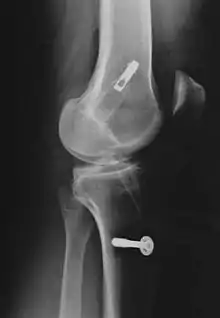

Pour la reconstruction du LC par transplantation autologue au moyen du tendon patellaire, une partie de celui-ci est prélevée avec des morceaux d'os aux extrémités, technique dite bone tendon bone (os tendon os), ou technique BTB. Il est tiré à travers des canaux élargis (8 à 10 mm de diamètre dans le tibia et le fémur). La longueur de chacun des blocs osseux est de 20 mm. L'ancrage le plus stable de la greffe est obtenu par fixation avec des vis d'interférence. Celui-ci est particulièrement important en vue d'une mobilisation fonctionnelle rapide.

Consolidation du transplant

Au début des années 1990, les transplants de tendons patellaires étaient fixés avec des vis d'interférence en titane soit aux deux bouts du transplant, soit uniquement au tibia, et fixés au fémur par un endobouton, enfilé sur le transplant. L'endobouton consiste en une bride de fil non résorbable munie d'une tête basculante en titane (plaque à quatre trous), que l'on bascule après un enfilage à travers le canal dans l'os[233]. Plus tard, on a utilisé des bioscrews (vis d'interférence résorbables) à la place des vis en titane[234], pour rendre une nouvelle opération d'enlèvement des vis inutile. Ces vis sont faites de polymères décomposables, comme un polylactide : Poly-L-lactide ou PLLA, ou poly-L-co-D/L-lactide ou PLDLLA. On peut aussi utiliser une technique hybride de vis résorbables (fixation intra-articulaire) et d'endobouton (fixation extra-articulaire). Dans la Press-Fit-Technik-Fixation, qui naît vers 1995, on peut complètement abandonner la fixation par les vis dans la technique BTB. Les extrémités osseuses sont usinées en cône, si bien qu'un bord-à-bord solide dans les canaux forés est possible. En 1996, on a utilisé des fraises commandées par robot pour faire ce joint, mais ce procédé n'a pu s'imposer en raison de son coût (en personnel et en appareils) et du manque de résultats indiscutablement meilleurs en opération.

Pour les transplants semi-tendineux et gracile (STG), on utilise le plus souvent des vis biodégradables pour la fixation. Depuis la fin des années 1990, on utilise aussi dans ce cas une fixation sans implantation[235]. Dans cette technique, le transplant semi-tendineux et gracile est noué à un bout. Le canal fémoral est creusé 4 mm plus étroit du côté articulation que de l'autre côté. Le transplant est alors introduit dans l'articulation à travers le canal fémoral. Là, le nœud du transplant se coince avant la partie plus étroite. Les mesures ont montré que la rigidité de l'articulation et la charge maximale atteignent des valeurs semblables à celles d'autres techniques. Par le nœud des bouts du tendon, les vis d'interférence deviennent superflues. Les partisans de cette fixation sans vis y voient un avantage de coût. Comme on n'utilise pas de vis, il ne peut pas y avoir de problème avec leurs matériaux[235]. Un inconvénient est cependant le canal significativement plus grand dans le fémur[1].